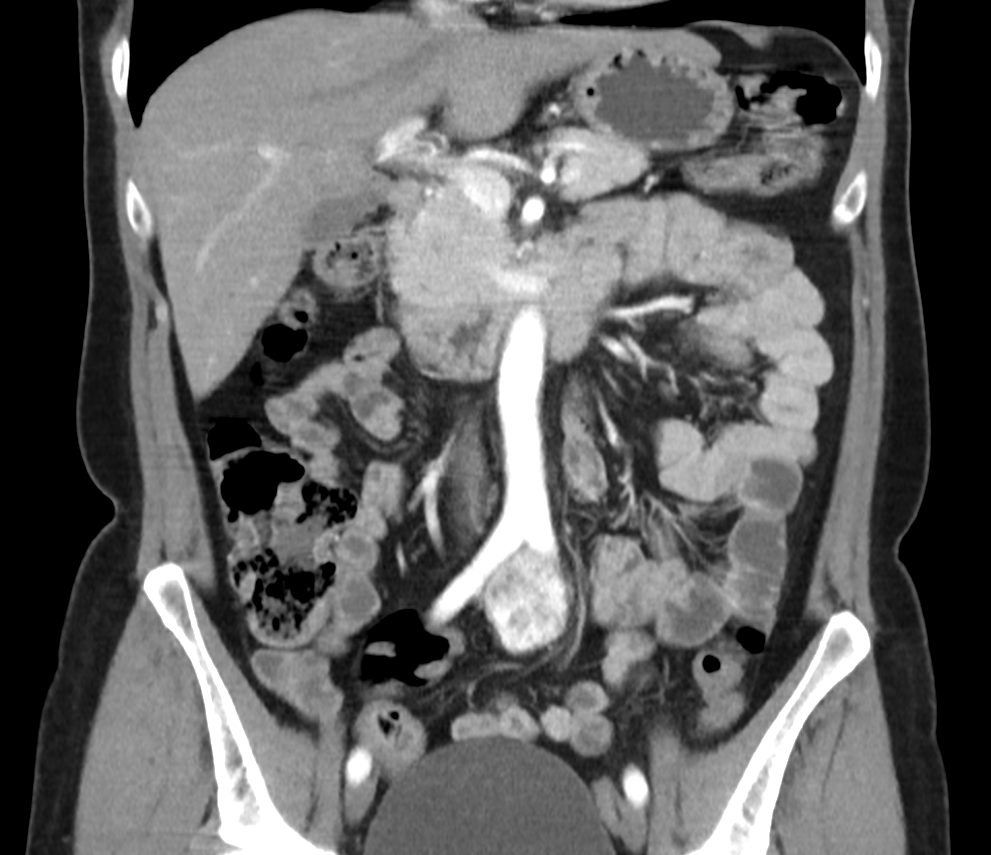

1. Рис. 1. КТ-ангиография органов брюшной полости и забрюшинного пространства до операции, артериальная фаза, фронтальная проекция. Примечание: рисунок выполнен авторами | |